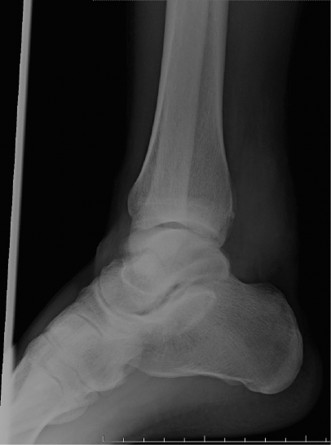

CASE 34 You see a 14-year-old girl in your clinic for the first time who has a …